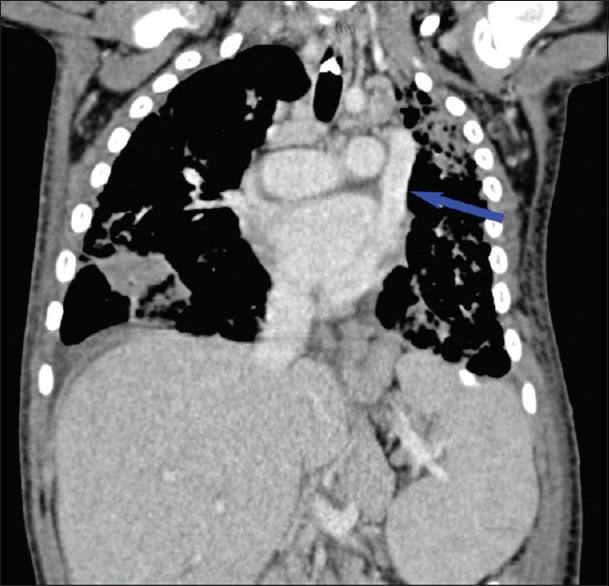

Waardenburg syndrome (WS) is a rare genetic disorder secondary to neural crest cell developmental abnormalities. It is predominantly described as an auditory-pigmentary syndrome with diverse patient presentation, typically involving congenital sensorineural hearing loss and pigmentation abnormalities of the skin, hair, and iris. Other developmental abnormalities that may be associated with this syndrome are Hirschsprung's disease and a myriad of cardiovascular congenital defects. We present a case of a young girl with WS who found to have a persistent left superior vena cava (PLSVC) draining into the coronary sinus. The prevalence of PLSVC is increased in patients with chromosomal and genetic abnormalities. However, we are the first to report its presence in association with WS while discussing the challenges that may arise during central venous catheter placement in patients with PLSVC.

瓦登伯革氏综合征(WS)是一种继发于神经嵴细胞发育异常的罕见遗传性疾病。它主要被描述为一种具有多种患者表现的听觉色素沉着综合征,通常包括先天性感音神经性听力损失以及皮肤、毛发和虹膜的色素沉着异常。可能与该综合征相关的其他发育异常包括先天性巨结肠和多种心血管先天性缺陷。我们报告一例患有WS的年轻女孩,发现其存在持续左上腔静脉(PLSVC)引流至冠状窦。PLSVC在染色体和基因异常患者中的患病率增加。然而,我们是首个报告其与WS相关的病例,同时讨论了PLSVC患者在中心静脉导管置入过程中可能出现的挑战。